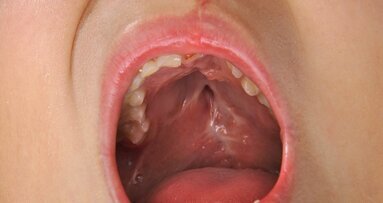

LOS ANGELES, U.S.: Despite their thriving market, electronic cigarettes may not be a harmless alternative to smoking after all. A recent study has shown that e-cigarette users develop some of the same cancer-related molecular changes in their oral tissue as cigarette smokers, adding to growing public health concern.

In the study, researchers at the University of Southern California (USC) analyzed gene expression in the oral epithelial cells of 42 e-cigarette users, 24 cigarette smokers and 27 nonsmokers to test for gene alteration, as certain alterations in gene expression can lead to cancer. Both smokers and vapers displayed abnormal expression, or deregulation, in a large number of genes linked to cancer development. About 26 percent of the deregulated genes in e-cigarette users were identical to those found in smokers. Some deregulated genes found in e-cigarette users, but not in smokers, are associated with lung cancer, esophageal cancer, bladder cancer, ovarian cancer and leukemia.

“The existing data show that e-cig vapor is not merely ‘water vapor’ as some people believe,” said senior author Dr. Ahmad Besaratinia, Associate Professor of Research Preventive Medicine at the Keck School of Medicine of USC. “Although the concentrations of most carcinogenic compounds in e-cig products are much lower than those in cigarette smoke, there is no safe level of exposure to carcinogens.”

Besaratinia noted that the molecular changes seen in the study are not cancer, or even pre-cancer, but rather an early warning of a process that could potentially lead to cancer if left untreated. The scientists are planning to replicate the study with a larger group of subjects and explore the mechanisms that cause gene deregulation. They are also launching another study in which smokers will switch to e-cigarettes to see whether any changes occur in gene regulation after the switch. “For the most part, the participants are as curious as we are to know whether these products are safe,” said Besaratinia.